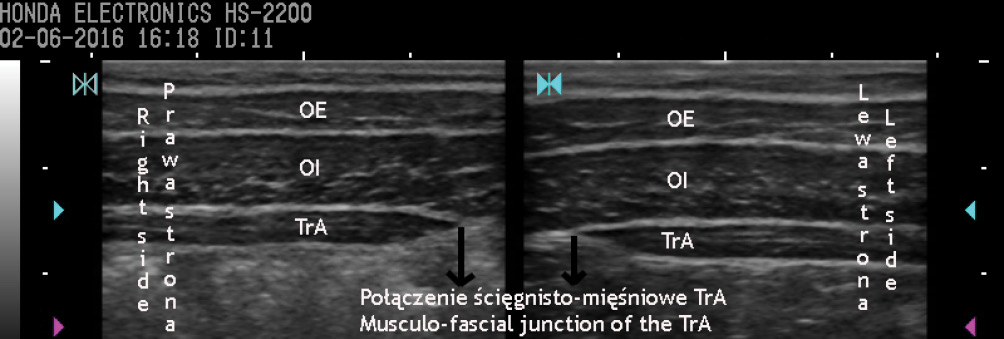

Ultrasonograficzna ocena morfologii mięśni bocznej ściany brzucha w badaniach naukowych – rekomendacje ogólne

Title: Ultrasound assessment of the muscles of the lateral abdominal wall in research – general recommendations

Streszczenie: Praca jest próbą dostarczenia niezbędnych informacji potrzebnych do właściwego przygotowania i przeprowadzenia badań naukowych obejmujących ultrasonograficzną ocenę mięśni bocznej ściany brzucha. Celami niniejszego przeglądu narracyjnego są: przedstawienie najczęstszych sposobów i warunków pomiaru mięśni bocznej ściany brzucha, określenie zmiennych warunkujących rzetelność tych pomiarów oraz wskazanie zmiennych zakłócających, które winny być kontrolowane w badaniach na różnych populacjach.

Summary: The paper attempts to provide necessary information in order to properly prepare and carry out research including ultrasound assessment of the muscles of the lateral abdominal wall. The aims of this narrative review are: to present the most common ways and conditions of the measurement of the muscles of the lateral abdominal wall, to specify the determinants of [...]